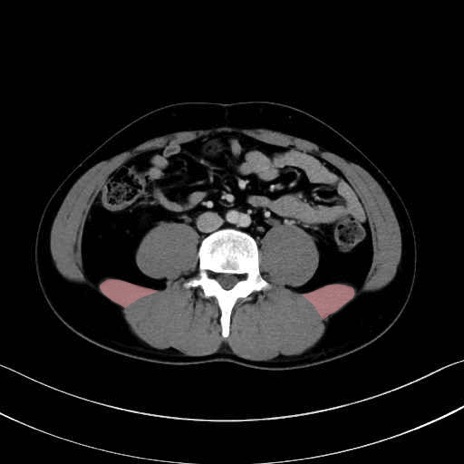

腰方形筋 (Quadratus lumborum)